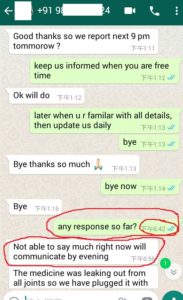

1. The Gentleman in Kenya started his treatment at his home April 27, now he said: (will update his more progresses soon)